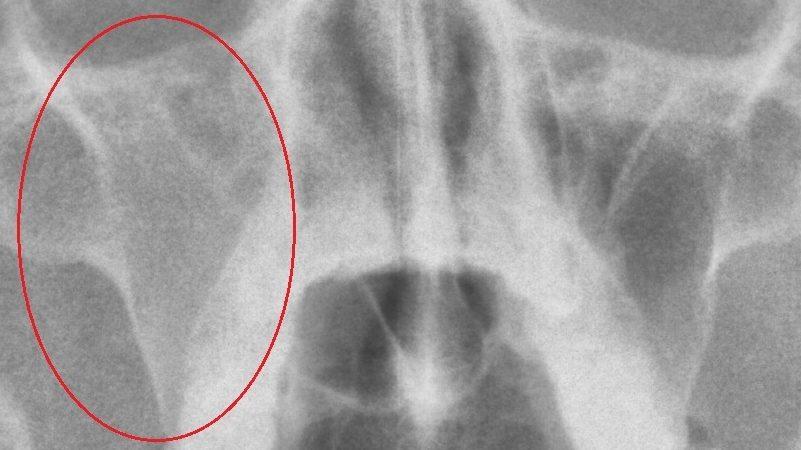

Если носовая полость пациента не имеет патологий и находится в здоровом состоянии, то рентгеновский снимок будет демонстрировать четкие контуры. На изображении можно увидеть тонкие и средние стенки ячеек решетчатого лабиринта. Пазухи же выглядят на рентгене как темные округлые участки.

В норме носовые пазухи должны обладать ясными и ровными очертаниями. Они не должны содержать светлых образований на темном фоне и наоборот.

Снимок может точно определить местоположение заболевания, что способствует более быстрому началу лечения. Если предполагается гайморит, то на рентгеновском изображении в носоподбородочной проекции будет видно затемнение верхних пазух, в которых присутствуют светлые участки, указывающие на наличие жидкости.

- На запущенной стадии заболевания затемнение будет находиться непосредственно над носом.

- При наличии темных участков в нескольких зонах, вероятнее всего, это фронтит.

- Гиперпластический синусит на снимке проявляется нечетким внутренним контуром слизистой оболочки рядом с костями.